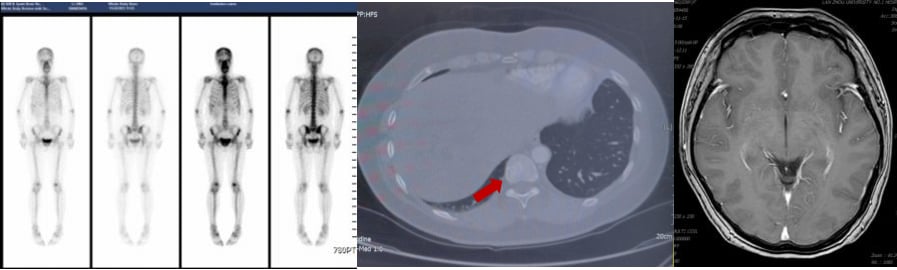

2025年2月,患者再次出现疾病进展,头颅MR显示左侧额顶叶异常强化软组织肿物,伴周围脑组织水肿,考虑脑转移。胸腹部CT显示肝脏病灶增大。

面对脑转移的再次出现,MDT团队决定启用新一代ADC药物——T-DXd(德曲妥珠单抗)。德曲妥珠单抗是目前HER2阳性乳腺癌治疗领域的一颗“新星”,它具有更高的药物抗体比(DAR),即每个抗体携带更多的化疗药物分子,同时具有“旁观者效应”,可以杀死周围未表达HER2的癌细胞。这使得它在治疗HER2低表达和脑转移方面展现出卓越的疗效。

患者接受了11周期的德曲妥珠单抗治疗。仅仅2周期后,患者右下肢无力症状明显好转;4周期后,右下肢肌力恢复,ECOG评分达到0分(意味着完全正常活动)。治疗过程中,骨髓抑制I-II度,胃肠道反应I度,未见间质性肺炎等严重副作用。影像学复查显示,疗效评价为部分缓解(PR)。这再次证明了创新药物在多线治疗失败后,仍能为患者带来显著的生存获益和生活质量改善。

3. 脑转移的治疗策略:全身治疗优先